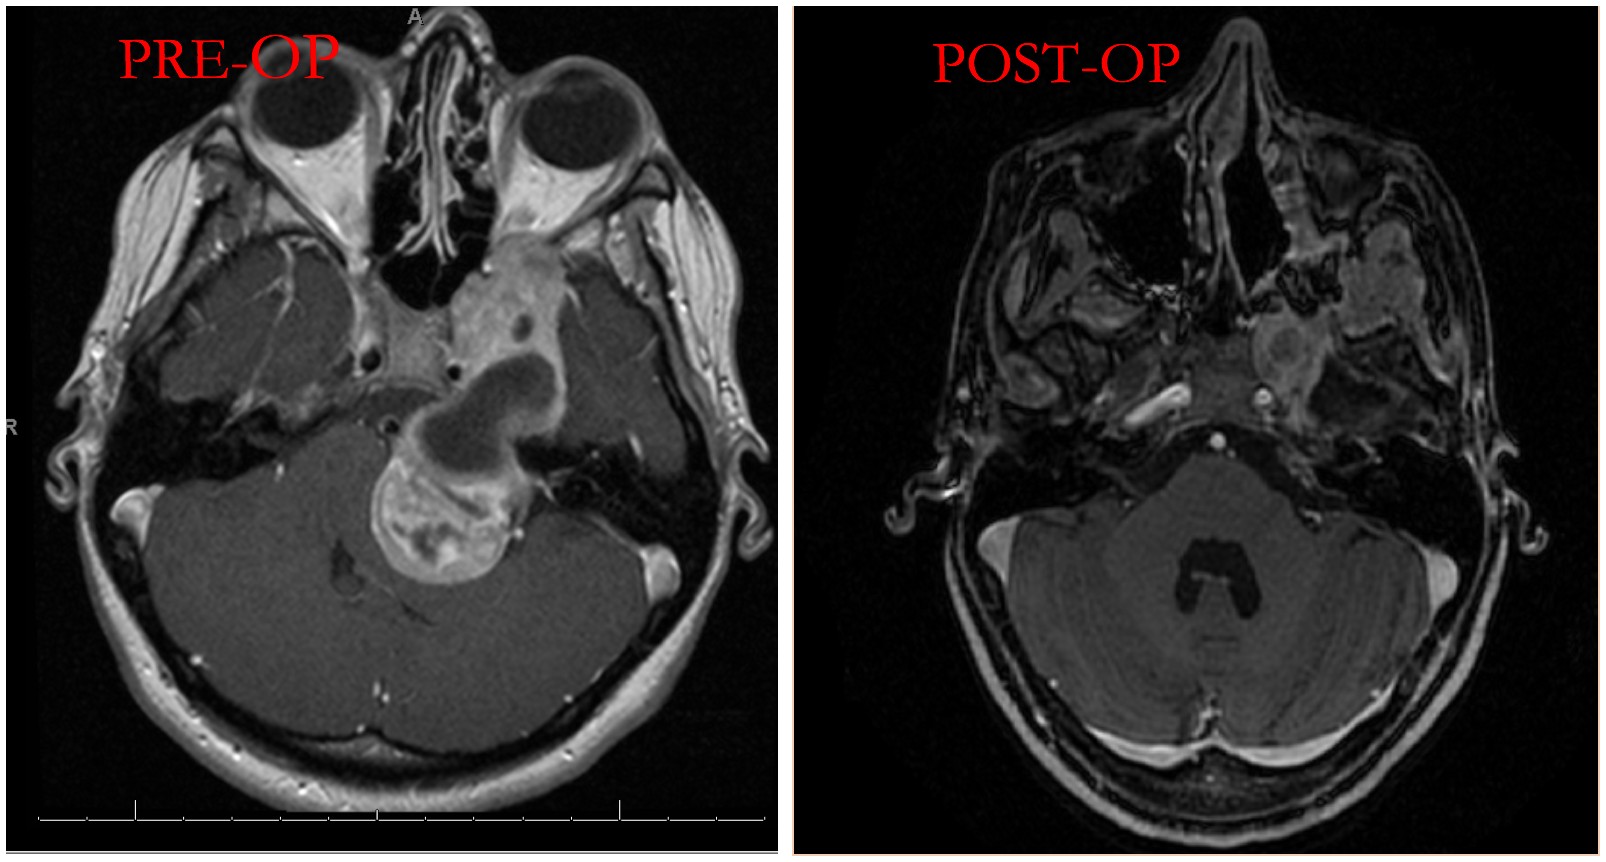

Our UMass Memorial Medical Center offers world-class care for skull base lesions. Neurosurgeons collaborating with otolaryngologists have developed a comprehensive open and endoscopic skull base surgery program where tumors located in challenging areas of the brain can be safely resected using minimally invasive techniques. In addition to minimally invasive techniques, our team is well-versed in all traditional approaches to the cranial base.

This vast expertise means our team can design the best treatment plan for any patient. The care of patients with skull base lesions requires a multidisciplinary approach to their care. UMass has developed a world-class team of surgeons, radiation oncologists, neuroradiologists and neuro-intensivists who provide excellent care to patients.

Together, they are pushing the envelope of where we can reach surgically.